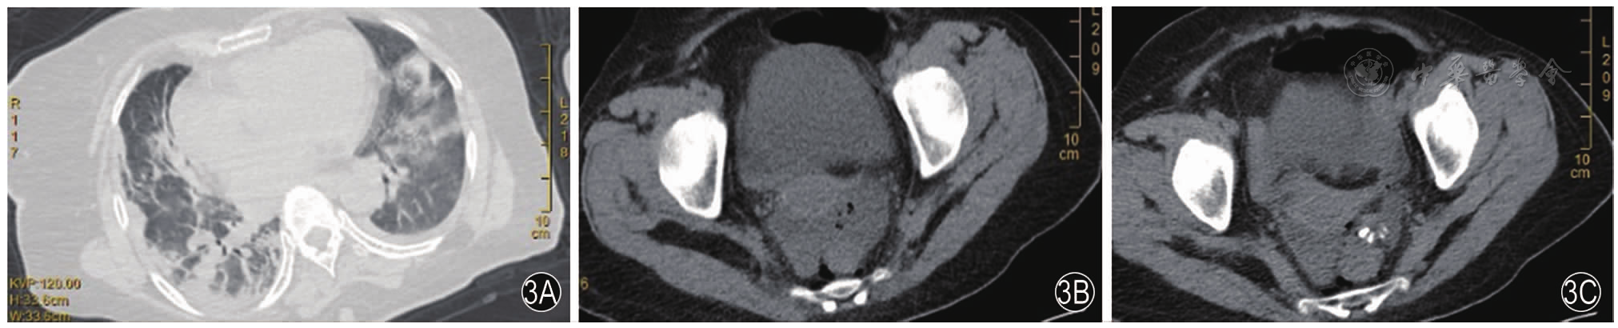

图4 术后第11天复查CT注:4A肺炎吸收;4B穿孔部位形成包裹性积液

图5 出院1个月后复查CT注:5A盆腔积液消失;5B钛夹消失